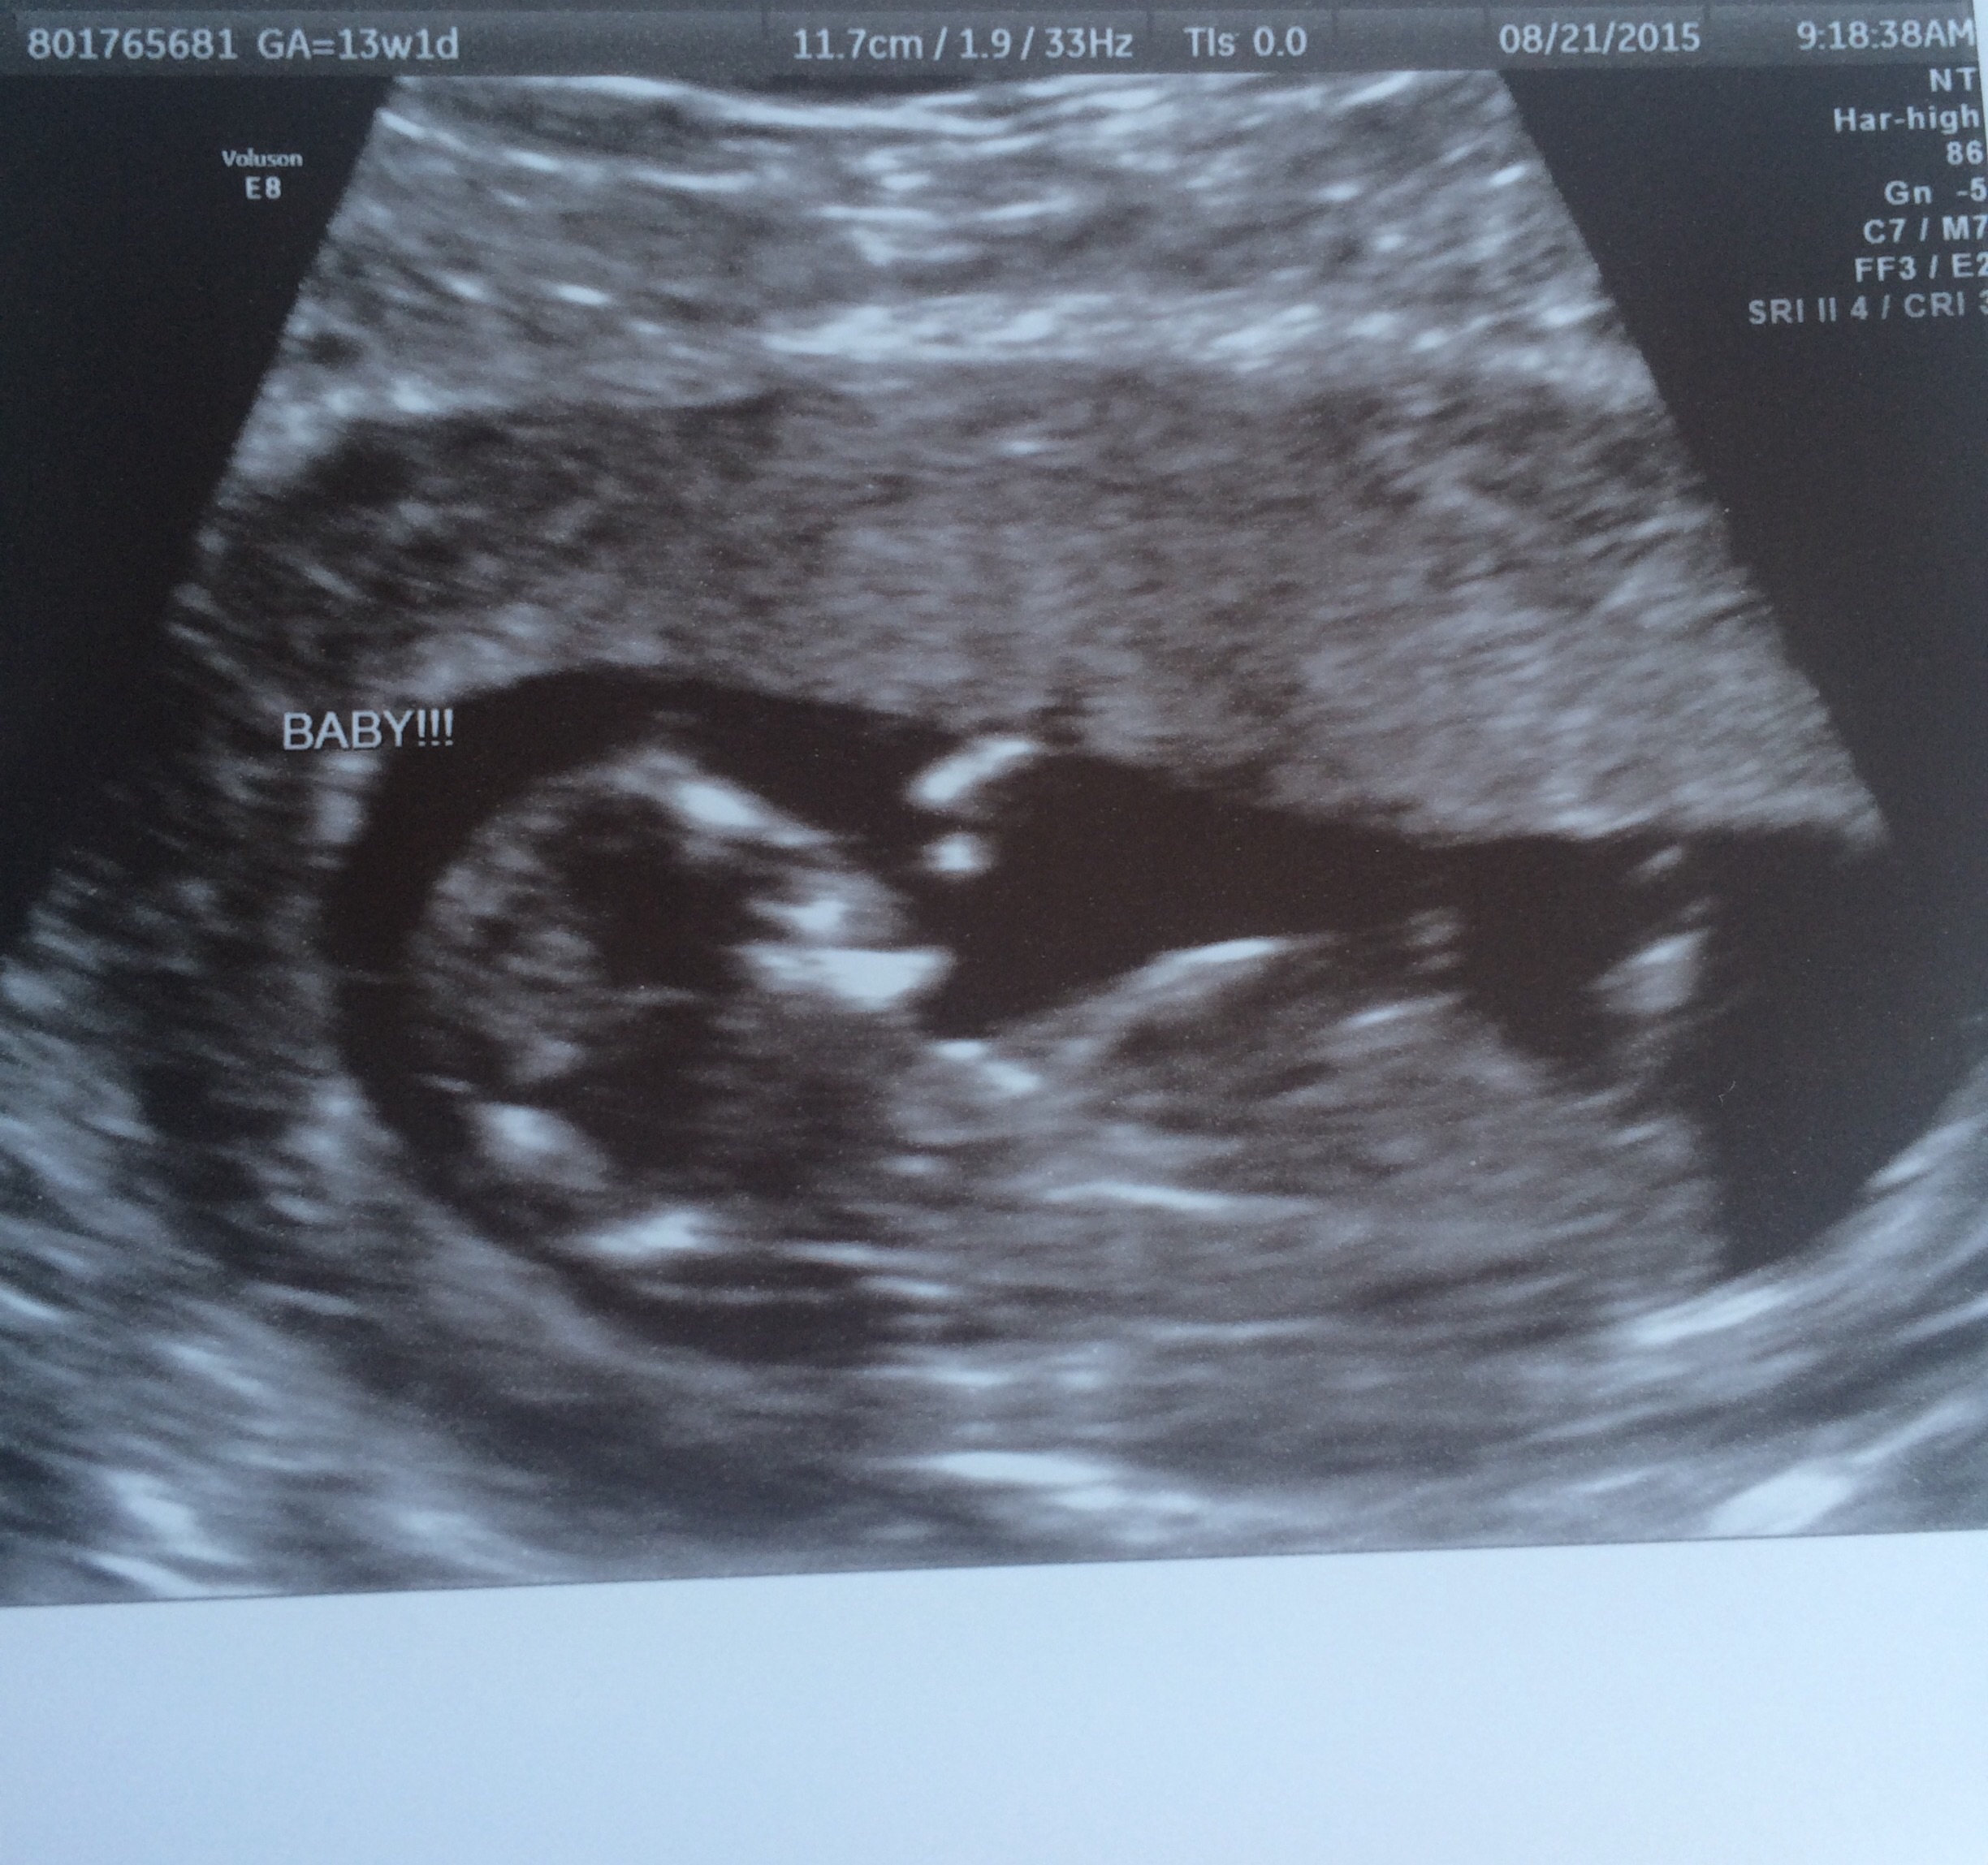

My husband and I are expecting our first baby, and we cannot wait to find out! We are going to have an elective ultrasound in two weeks, but I wanted to post my ultrasound here to get everyone's thoughts! We will be so happy either way! This is from my ultrasound at 13 weeks and 1 day. The baby was wiggling around a lot, but here is the clearest image I have.